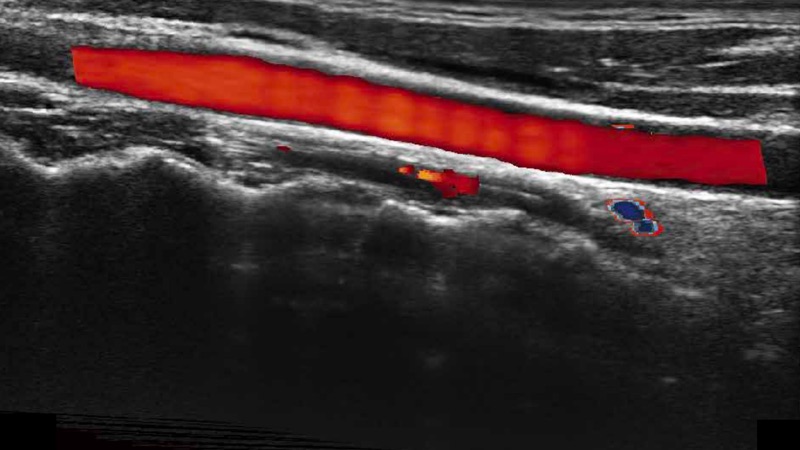

高分辨率血流成像技術(shù)提高了對低速血流信號的檢測能力。在提高空間分辨率的同時,也克服了血流外溢現(xiàn)象,為用戶提供更加真實的血流動力學(xué)信息。

凸陣、線陣和相控陣探頭進(jìn)行實時掃描時,開啟擴(kuò)展成像模式,可以擴(kuò)展超聲圖像視野,以便更完整地查看大的病灶或組織器官的解剖結(jié)構(gòu)。

通過色彩血流和實時寬景相結(jié)合,可觀察到完整的靜脈或動脈的血流,方便醫(yī)生檢查。實時掃查過程中,如有任何操作失誤也可以很容易地進(jìn)行回掃擦除,而不會中斷掃查。

自動識別前后壁內(nèi)膜厚度,為心血管疾病早期評估提供快速準(zhǔn)確依據(jù)。